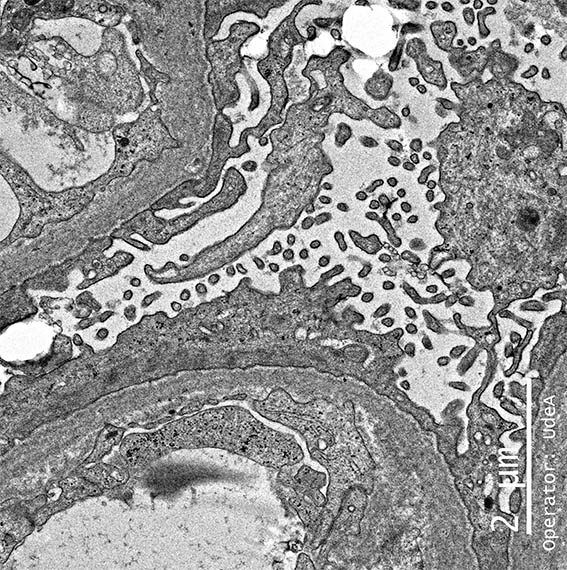

Figure 7. EM, original magnification, X2,500.